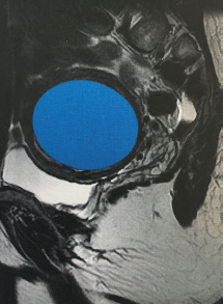

Estan formats per cèl·lules musculars i altres teixits que creixen dins i al voltant de les parets de l'úter.

Segons la seva localització, els miomes es classifiquen en:

- intramurals: creixen dins de la paret muscular de l'úter

- Submucosos: creixen cap a l'interior de l'úter i deformen la seva cavitat

- Subserosos: creixen i es projecten cap a l'exterior de l'úter